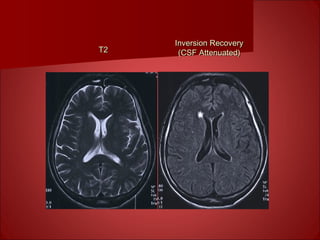

Inversion Recovery for Extra T1Inversion Recovery for Extra T1

ContrastContrast

T2T2

Inversion RecoveryInversion Recovery

(CSF Attenuated)(CSF Attenuated)

In summary, TR controls T1 weighting andIn summary, TR controls T1 weighting and

TE controls T2 weighting. Short T2 tissuesTE controls T2 weighting. Short T2 tissues

are dark on T2 images, but short T1 tissuesare dark on T2 images, but short T1 tissues

are bright on T1 images.are bright on T1 images.